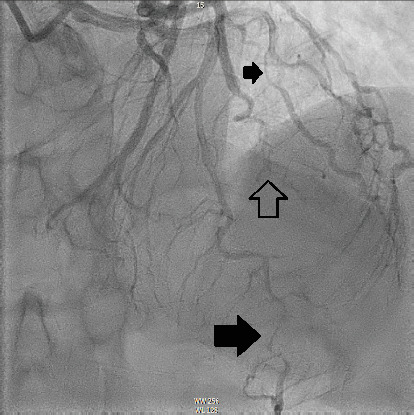

The management of spontaneous coronary artery dissection (SCAD) presents challenges and uncertainties. We present a case of a 54-year-old woman who developed SCAD in the three primary coronary artery territories including the distal left anterior descending artery (LAD), a diagonal branch, the first and second obtuse marginals (OMs), and the midright coronary artery (RCA). She was managed conservatively without procedural intervention, and follow-up coronary angiography demonstrated complete recovery.

自发性冠状动脉夹层(SCAD)的治疗存在挑战和不确定性。我们报告了一例54岁的女性,她在三个主要冠状动脉区域发生了SCAD,包括左前降支远端,对角分支,第一和第二钝缘(OMs)和右冠状动脉(RCA)。患者接受保守治疗,无手术干预,随访冠状动脉造影显示完全恢复。